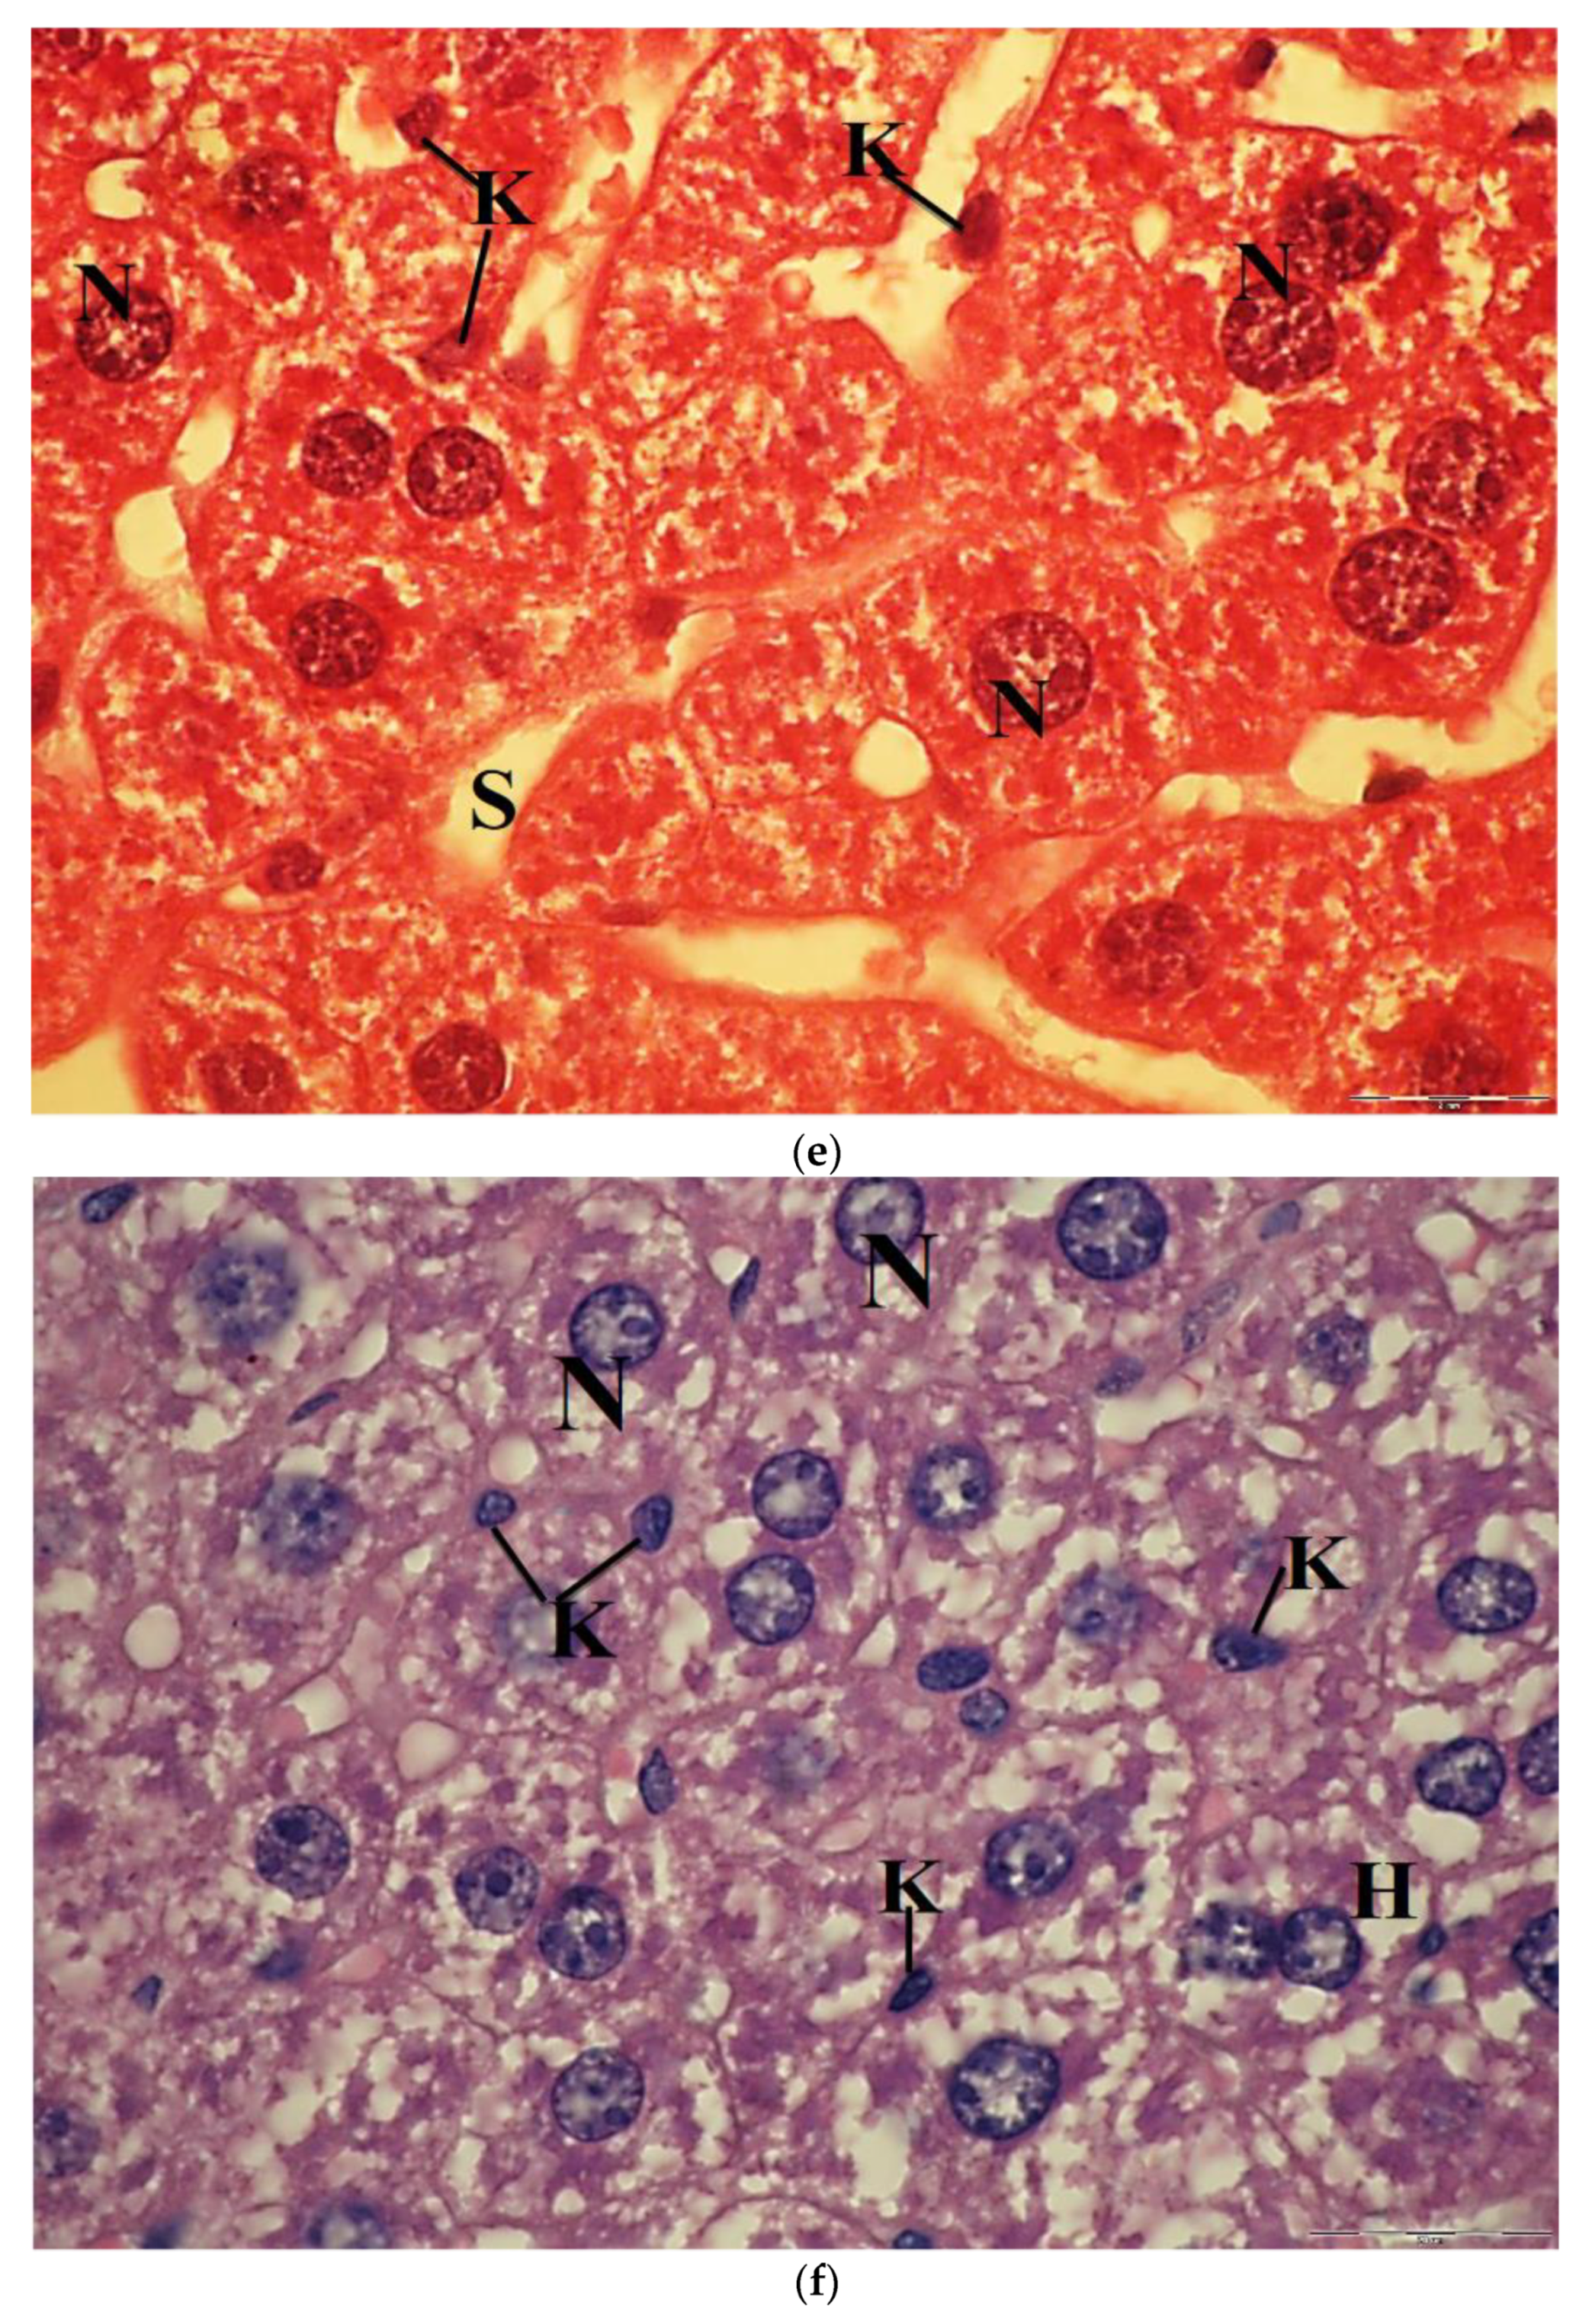

Sections of liver mice treated with 100 mg/kg CuNPs showed that the hepatocytes were more or less similar to the control. In a few sections, they had lost their characteristic organization, and the cytoplasm was slightly vacuolated. The nuclei were vesicular and displaying their normal shaped structures. Kupffer cells appeared few and showing a marked decrease in their sizes (Figure 8c). However, the light micrographs of liver sections of mice administered with 250 mg/kg CuNPs showed severe congestion and dilatation of the blood vessels, in addition to the massive lymphocytic infiltration around them. Most of the hepatocytes were greatly damaged, exhibiting severe vacuolation, and had lost their acidophilic substances. Moreover, the nuclei in most hepatocytes were displaying pyknosis, and few small-sized Kupffer cells were observed (Figure 8d).

Furthermore, the hepatocytes in sections of liver mice treated with 100 mg/kg CuNPs + 60 mg/kg ESE showed no evidence of damage compared to those treated only with 100 mg/kg CuNPs. However, an observable dilatation in the hepatic sinusoids was seen (Figure 8e). The light micrographs of liver mice treated with 250 mg/kg CuNPs and 60 mg/kg ESE showed that the hepatocytes normally appeared in their polygonal-shaped structure. Their nuclei were vesicular and displaying their normal shaped structures as well as the control. The Kupffer cells were normal in shape (Figure 8f).

In the current study, the cytotoxicity of CuNPs was evidenced by the appearance of morphological changes in liver cells, such as congestion and dilatation of the blood vessels, the presence of much inflammatory infiltration in pre-central veins, as well as the appearance of hepatocellular necrosis. These alterations were prominent in the liver tissues of mice administered with 250 mg/kg of CuNPs. However, the decrease in these degenerative changes in the liver of mice was apparent in the liver tissues of mice treated with ESE. Our present study, parallel with Kim et al. [46], reported some histopathological changes and increased infiltration around the central vein induced by nanoparticles. The destruction of lobular structure and vacuolization of hepatocytes together with the dilatation of the central vein and blood sinusoids indicate that these NPs may affect the permeability of the cell membrane in hepatocytes and the endothelial lining of blood vessels [66]. Additionally, the appearance of inflammatory cells in hepatic tissue suggests that nanoparticles can interact with proteins and enzymes in the interstitial tissue of the liver, interfering with the antioxidant defense mechanism and leading to the generation of ROS, which in turn may induce an inflammatory response [67].

The obtained results are consistent with the previous findings of Doudi and Setorki [19] who found that 100 mg/kg CuNPs induced histological changes in the hepatic tissues, vasculature in the central vein, and the disappearance of hexagonal liver lobules which is lined with the present study. Moreover, the destruction of the lobular structure, vacuolization of hepatocytes (fat deposits), and congestion of RBC, and infiltration of leukocytes in the liver tissue of mice administered with 300 mg/kg ZnNPs, indicating its necrotic effects [56].

Figure 8. (a) Light micrograph of mice liver of control group showing, the vesicular spherical nuclei (N), binucleated hepatocytes (arrow); hepatic sinusoids (S); triangular-shaped Kupffer cells (K), H&E, ×1000. (b) Light micrograph of liver mice treated with 60 mg/kg bw of ethanolic saffron extract, showing polygonal hepatocytes (H); vesicular nuclei (N); wide blood sinusoids (S); many activated Kupffer cells (K), H&E, ×1000. (c) Light micrograph of liver mice treated with 100 mg/kg bw of CuNPs showing vacuolated hepatocytes; nuclei (N); few leucocyte infiltrations (thick arrow) and small size Kupffer cells (K), H&E. ×1000. (d) Light micrograph of liver mice treated with 250 mg/kg bw of CuNPs showing degeneration and vacuolated hepatocytes; pyknotic nuclei (arrowheads); Kupffer cells (K), H&E, ×1000. (e) Light micrograph of liver mice treated with 100 mg/kg bw of CuNPs + 60 mg/kg bw ethanolic saffron extract showing polygonal-shaped hepatocytes containing vesicular nuclei (N). Note: dilated blood sinusoids (S) and few small-sized appearances of Kupffer cells (K), H&E, ×1000. (f) The light micrographs of liver mice treated with 250 mg/kg bw of CuNPs + 60 mg/kg bw ethanolic saffron extract showed vacuolated hepatocytes (H) with vesicular nuclei (N) and Kupffer cells (K), H&E, ×1000.